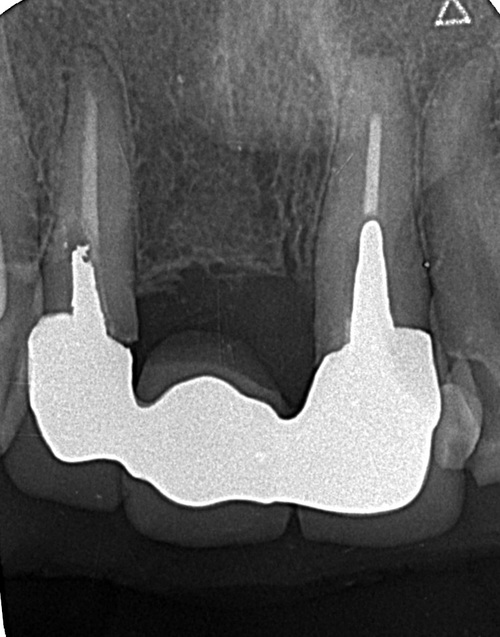

こちらが初診時のレントゲンとお口の写真になります。

右上の1番目の歯がすでになく、右上の2番目と左上の1番目の歯でブリッジが入っている状態です。ブリッジは、他の歯の色に比べ、白く不自然な色となっています。さらに、左上1番目の歯茎が腫れてしまっているのが良くわかります。

患者様のお口の中を診察させていただき、レントゲン写真を撮影して、現在の歯の状態について詳しく調べました。調べた結果、ブリッジを支えている左上1番目の歯の根にヒビが入っている状態(歯根破折)でした。歯根破折が生じた歯は、ヒビに沿って細菌が感染し、周りの骨が溶かされ、歯茎が赤く腫れ上がり炎症を起こす原因となるため、抜歯が必要となります。